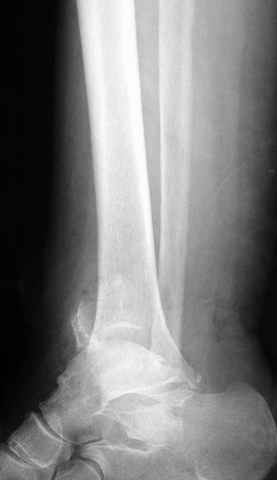

Традиционная техники АО, открытая, с точной репозицией суставной поверхности и жесткой фиксацией, из-за серёзных осложнений, которые

заканчивались ампутацией, уходит в прошлое.

Техника сегодня более щадящая, временные несложные аппараты наружной фиксации: Spanning 2 pin ExFix, Traveling traction для лигаментотаксиса, иначе сокращенные мягкие ткани невозможно восстановить позже.

За последнее 10-12 лет после стабилизации малоберцовой кости, стали применять более усовершенный, сложный, хорошо вам известный метод

Илизарова (кстати наряду с тибиал плато, пилон является одним из показанием по применению аппарата Илизарова при травмах) или Hybrid

Fixator, из минимальных доступов комбинированный метод для восстановления суставной поверхности-фиксация каннулированными

шурупами, создания жесткой системы фиксации до сращения перелома, защита от вальгусной деформации и на место образовавщегося метафизарного дефекта- костная пластика ауто костью или его

синтетические заменители, это сегодняшная тактика лечения.